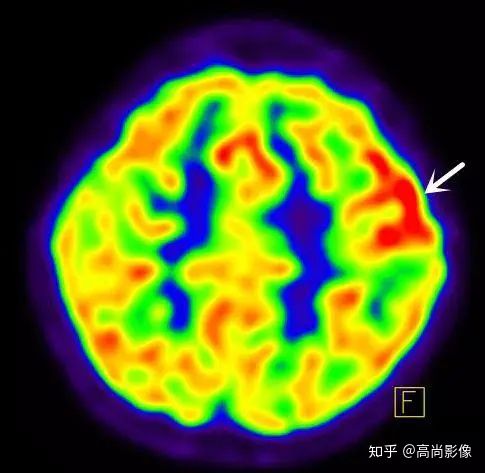

局部18F-FDG代謝顯像主要應(yīng)用于無創(chuàng)定位癲癇病灶。

在國際上,18F-FDG代謝顯像是無創(chuàng)定位癲癇病灶的標準。

發(fā)作間期癲癇灶呈代謝減低

發(fā)作期癲癇灶呈代謝增高